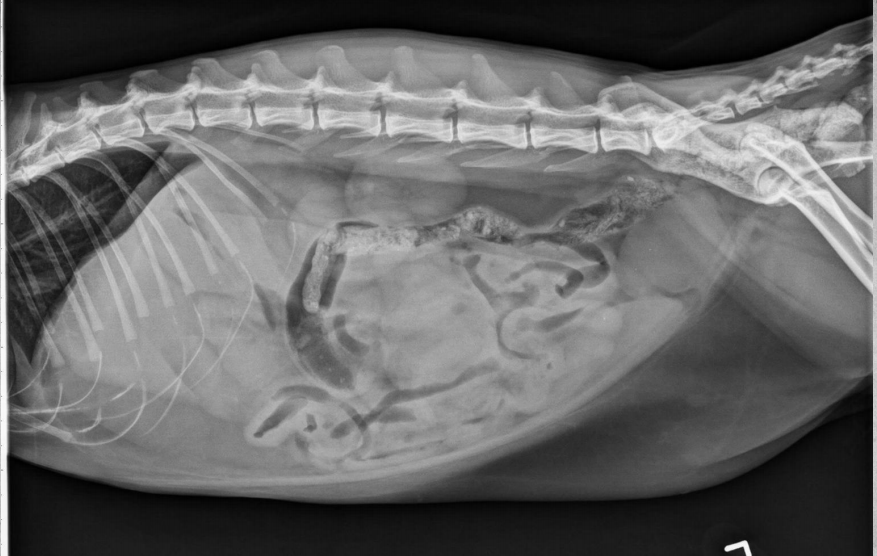

15 yo cat

Weight loss, anorexia, vomiting

Findings:

● Dilated bowel filled with fecal mass

– Not only large intestine, but small

intestine as well.

● Megacolon